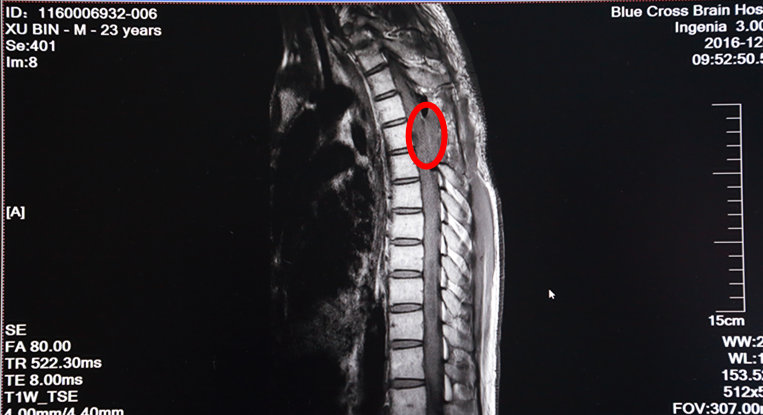

術后MRI增強掃描:紅圈內(nèi)腫瘤物已消失

次日,手術進行。術中,在全麻下打開硬脊膜,手術顯微鏡下,脊髓表面見大量迂曲的血管團,選擇血管相對稀少而功能不是很重要的區(qū)域切開薄如薄紙的脊髓,小心沿腫瘤邊緣分離并逐次切斷供應腫瘤的血管,順利地完成了腫瘤的全切除。術后增強MRI示腫瘤已經(jīng)全部切除了。